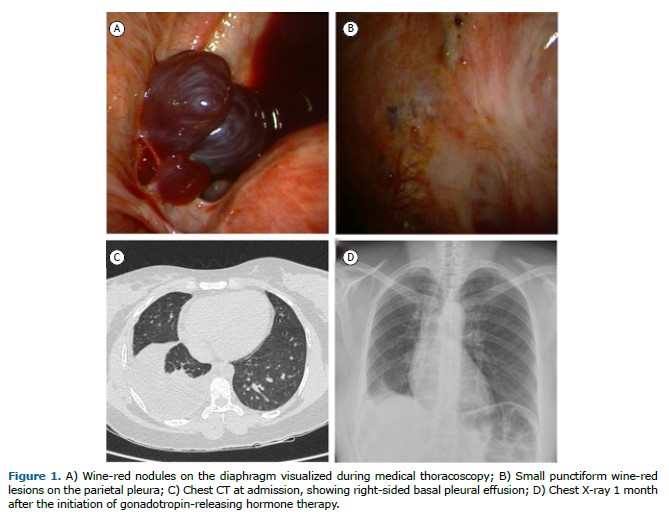

A 38-year-old Brazilian woman with a previous diagnosis of pelvic inflammatory disease presented to our hospital with a two-month history of dyspnea, chest pain, and dry cough. Chest CT revealed right-sided basal pleural effusion. The QuantiFERON-TB test result was positive. On the basis of those findings and the symptoms, we suspected a diagnosis of pleural tuberculosis. An explorative thoracentesis was performed. The aspirated pleural fluid was hemorrhagic. The cytological examination showed a predominance of histiocytes and leukocytes, and no malignant cells were detected. At that point, we decided to perform medical thoracoscopy to obtain biopsy specimens from the parietal pleura. The procedure revealed thickened pleura and small, wine-red lesions on the diaphragm and parietal pleura (Figure 1), findings suggestive of pleural endometriosis. Histopathological analysis confirmed the presence of epithelial glandular elements, and immunohistochemical staining was positive for CD10 and estrogen receptors. Thoracic endometriosis presents nonspecific symptoms, making the diagnosis challenging. In women of reproductive age presenting with chest pain and pleural effusion, endometriosis should be considered as a possible cause. (1) Hormone suppression therapy with gonadotropin-releasing hormone analogs can help alleviate symptoms as well as improving the overall quality of life and daily functioning. (2) Early recognition and multidisciplinary care are key to achieving better outcomes.(3)